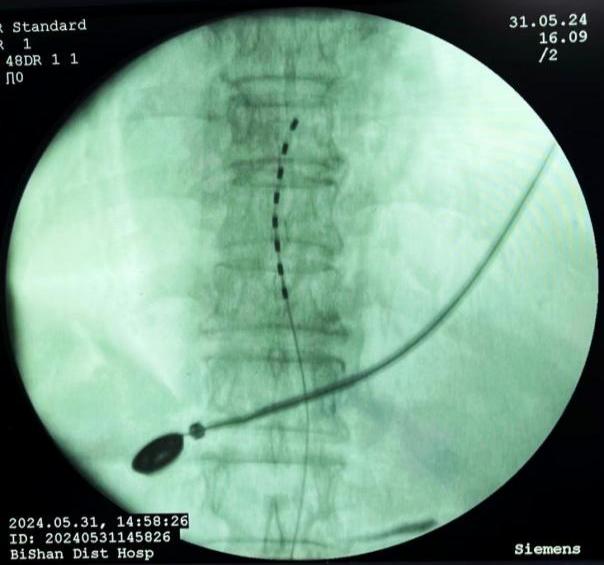

790f9d137fc5439d8234242aa944f998.Jpeg  a7d6b1926c8546598ed78915915a896e.Jpeg

鞘內(nèi)泵植入術(shù)